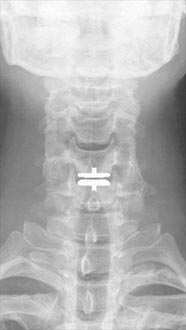

35 year old man presenting with severe neck pain with radiation down the right arm with right bicep weakness. MRI with large right C5-6 disc extrusion.

Postoperative xrays after C5-6 anterior cervical disc replacement. Complete resolution of arm pain and full painless range of motion of his neck.